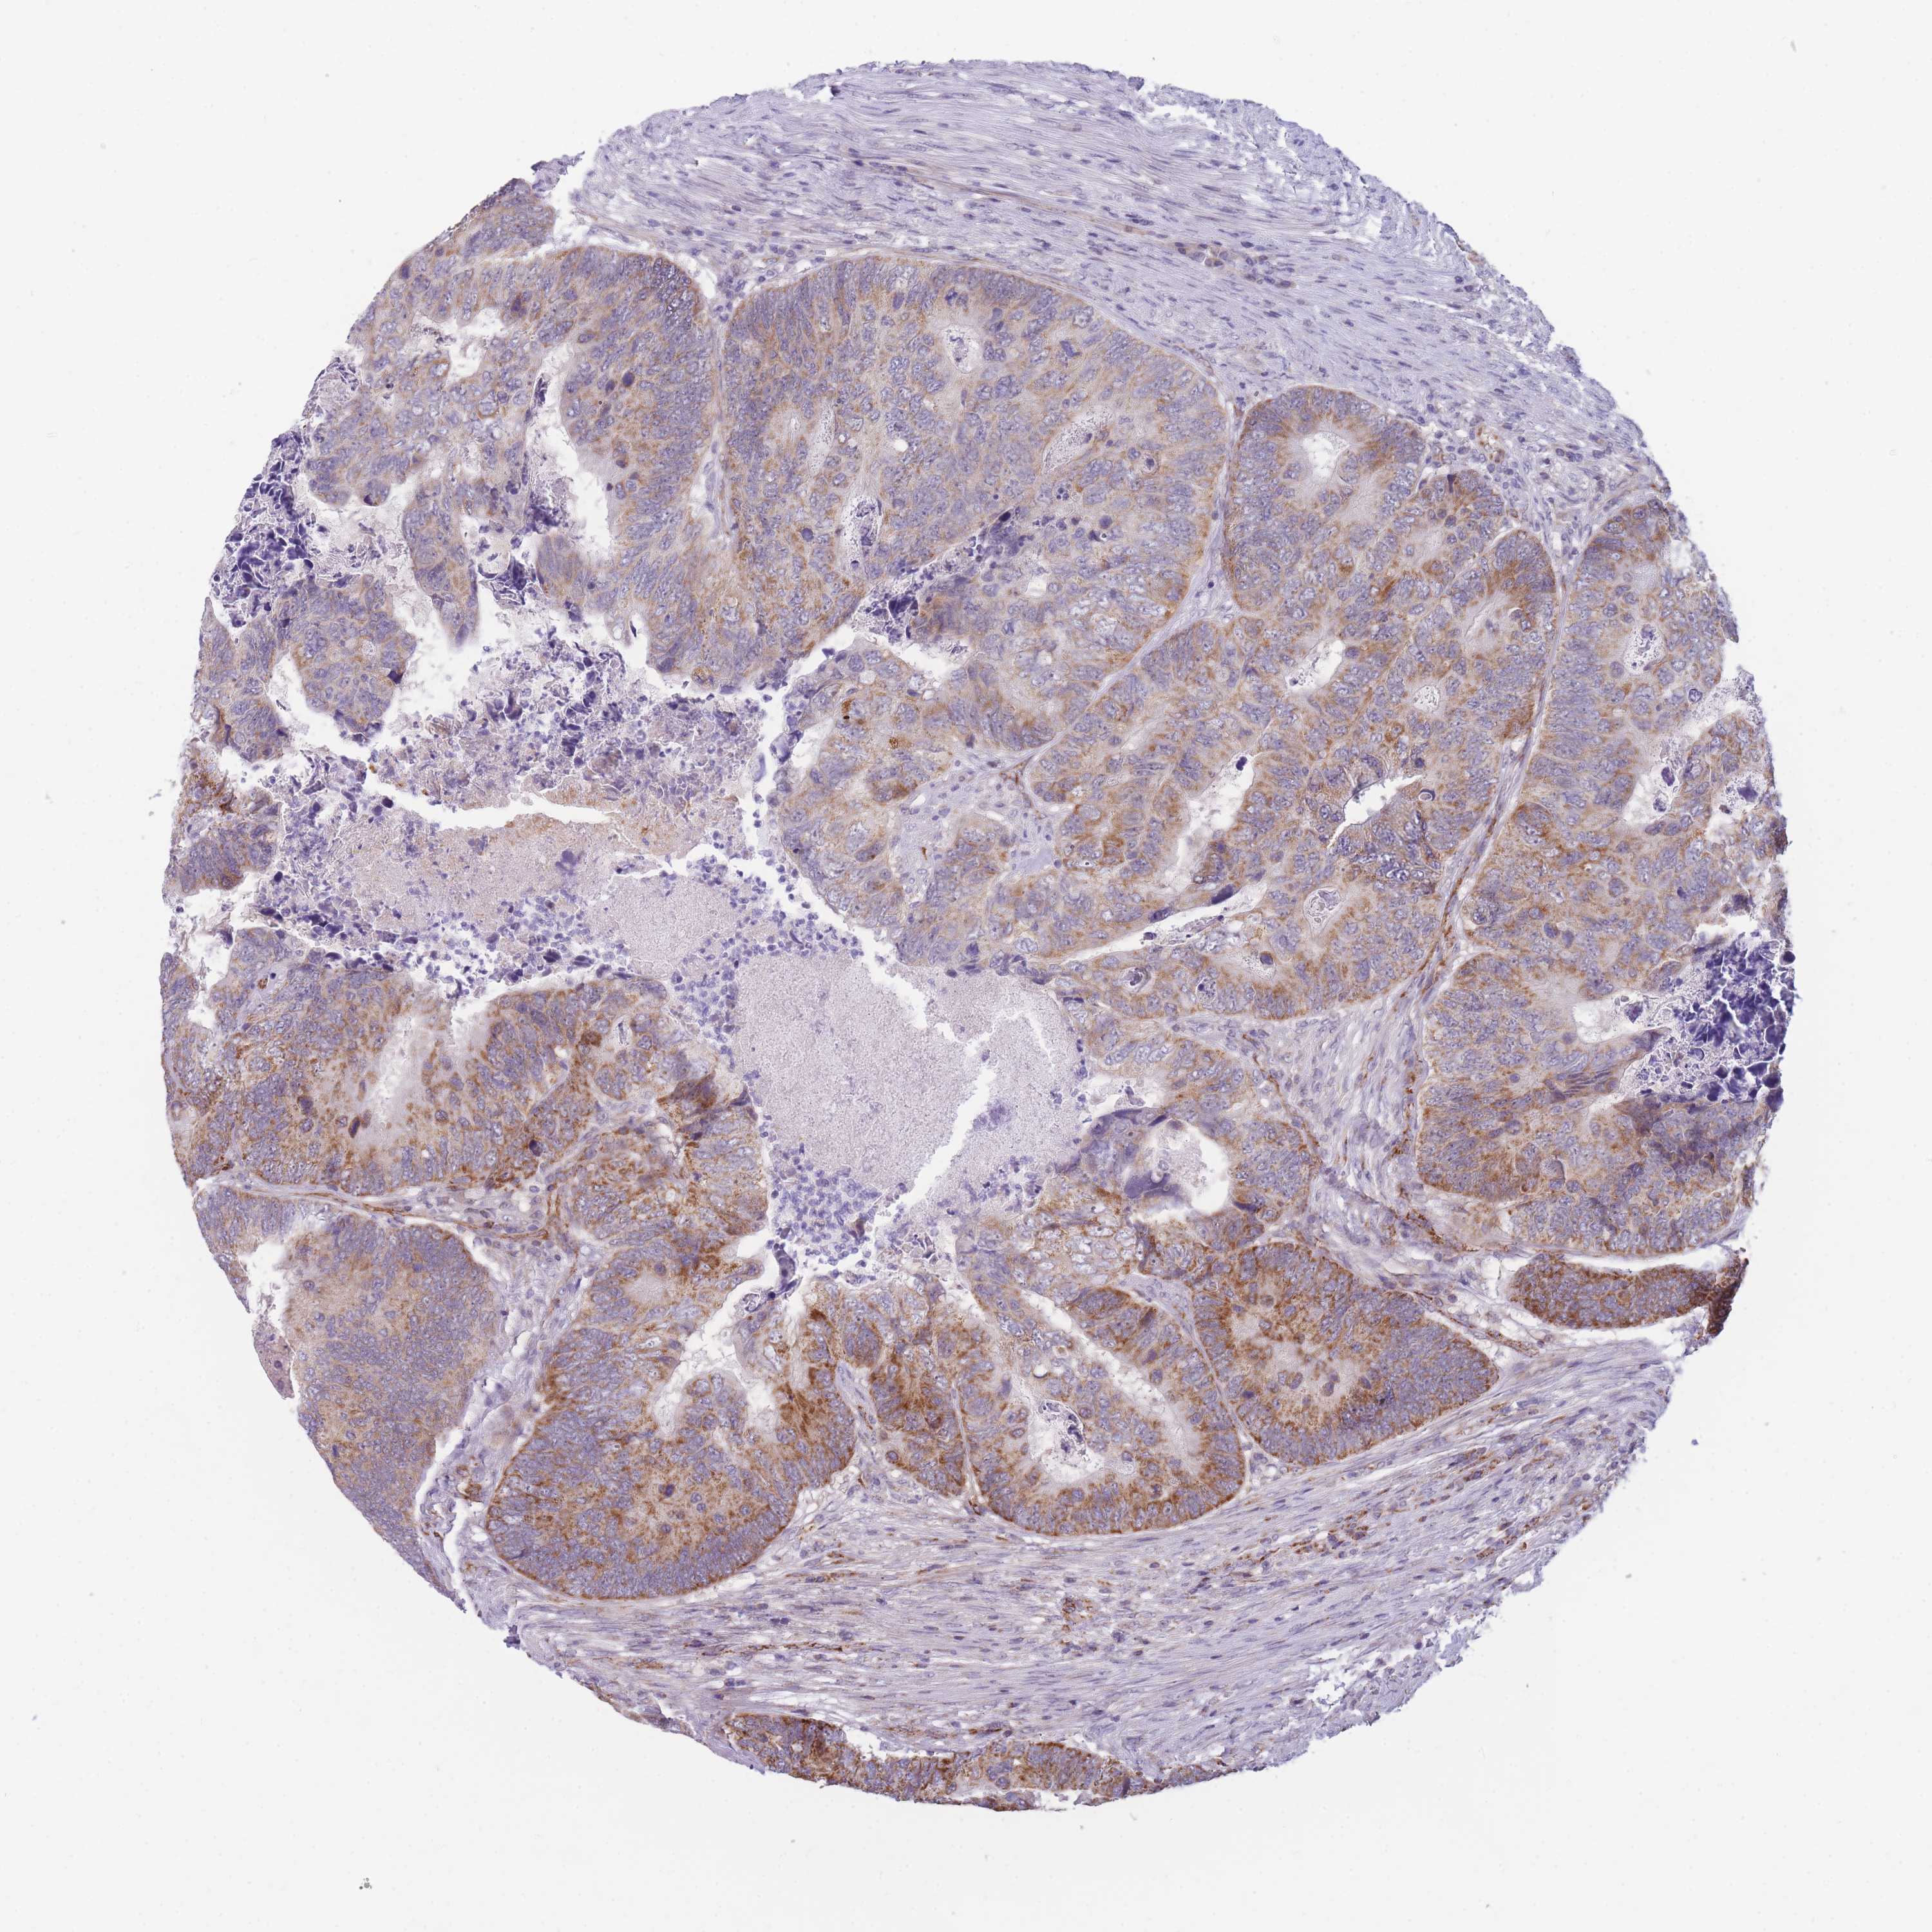

Colorectal cancer

Colon adenocarcinoma